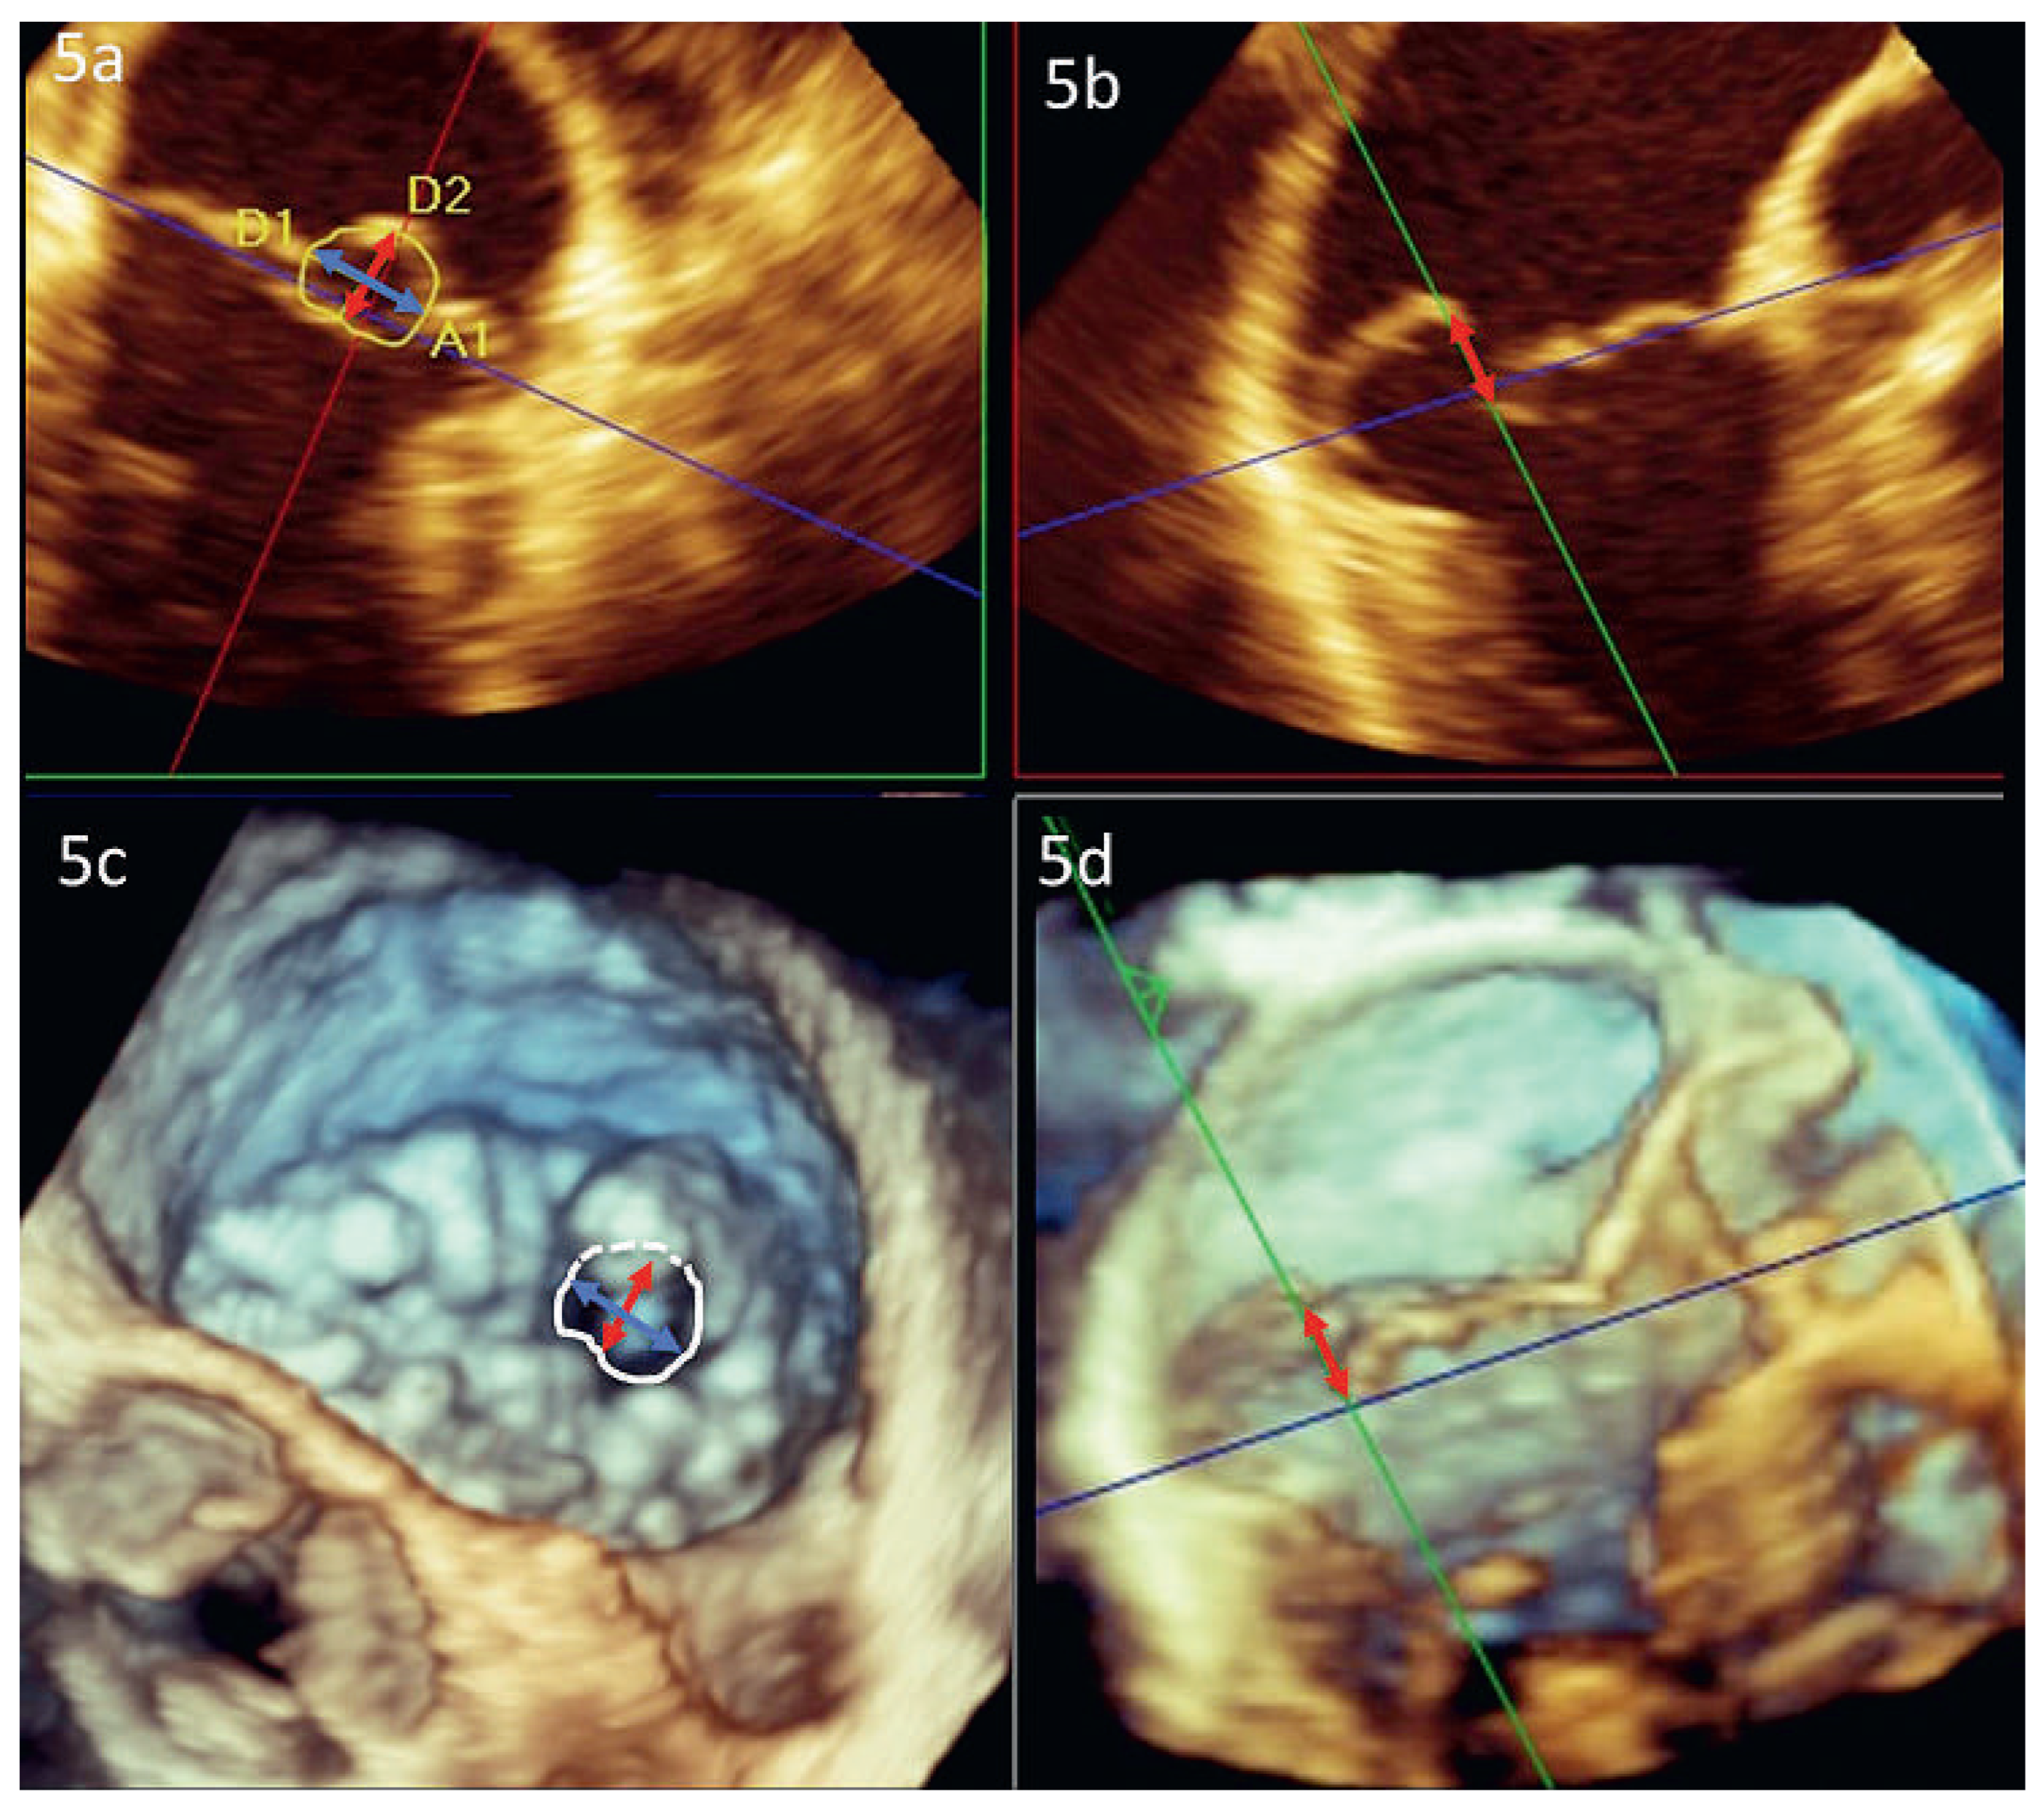

In den letzten Jahren sind verschiedene dreidimensionale transthorakale und transesophageale Methoden zur Quantifizierung der Mitralinsuffizienz entwickelt worden: Die 3D-VC-Area (Abbildung 4d) [19], das 3D-Regurgitationsvolumen [20], die 3D-Planimetrierung der anatomischen ROA (AROA, Abbildung 5) [21] sowie die 3D-Color-DopplerEchokardiographie mit Flussvolu-metrie (s. Abbildung 6) oder mit 3D PISA-Methode [22]. Alle Methoden überzeugen gegenüber den 2D-Berechnungen, weil sie nicht mehr auf geometrischen Annahmen basieren und damit einen gewichtigen Fehler ausschalten. Prinzipiell ermöglichen sie auch die Quantifizierung von komplexen und multiplen Regurgitationsjets. Die reduzierte zeitliche und räumliche Auflösung sowie die teilweise sehr zeitaufwändigen Techniken limitieren jedoch deren breite Anwendung im Alltag. Speziell die 3D-PISA-Methode mittels der neu entwickelten single-beat real-time 3D-Color-Doppler-Technik ist eine vielversprechende Methode bei Trikuspidal- [23] und Mitralinsuffizienz [24]. Dies insbesondere daher, weil erstmals die verschiedenen Beschleunigungsareale, welche über die Zeit entstehen, integriert werden und damit der Zeitpunkt der Messung nicht mehr ins Gewicht fällt. Bisher sind die Arbeitsschritte dieser Methode aber noch nicht vollautomatisiert. Es müssen immer noch betrachterabhängige Korrekturen gemacht werden, welche die Reproduzierbarkeit auch dieser Methode limitieren.

Abbildung 5. Anatomische Regurgitationsfläche (AROA) bei Mitralklappenprolaps 3D-Rekonstruktion der Mitralklappe mittels zusätzlicher Software (3D Quantification Software 8.1, Philips Ultrasounds). Abb. 5a: 2D-Darstellung der AROA (gelb markiert). Roter und blauer Pfeil: max. Höhe und Breite. Abb. 5b: Längsachse: Diese Ebene steht senkrecht zur blauen Achse in 5a. Roter Pfeil: Max. Höhe des Prolaps. Abb. 5c: 3D-Darstellung der Klappe. Die AROA ist deutlich abgrenzbar (weisse Markierung), ebenso die Durchmesserlinien. Abb. 5d: 3D-Darstellung des Prolaps analog zu 5b.